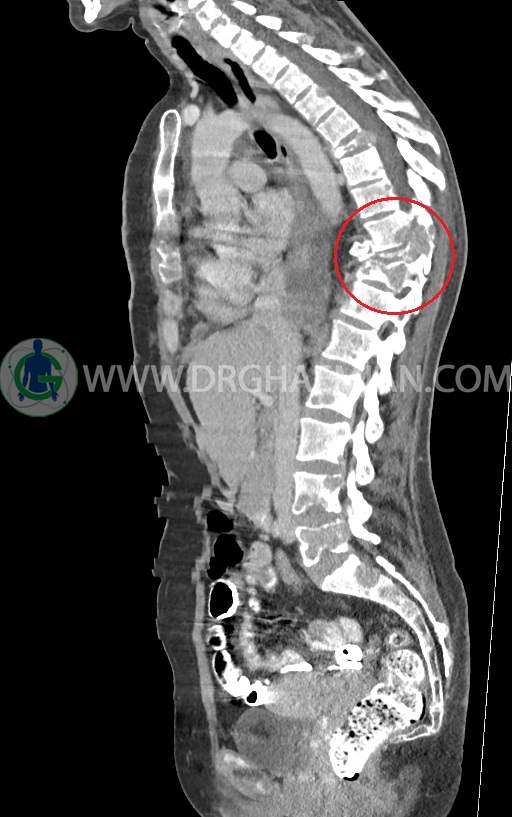

–ضایعات استخوانی لیتیک فراوان منتشر در تمامی طول ستون مهره و لگن رویت شدند که مطرح کننده متاستاز استخوانی می باشند.

–شکستگی پاتولوژیک در مهره های T6 , T10 , T11

–کیفوز موضعی در Level T10 , T11 در ستون مهره

–رتروپالشن شکستگی مهره T10 همراه با ایجاد تنگی کانال نخاعی